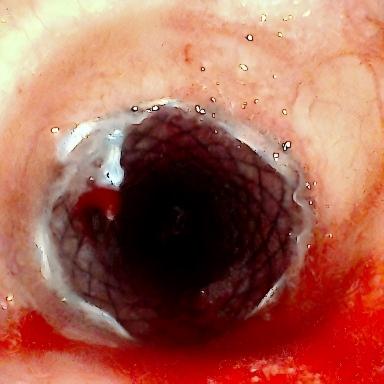

方案确定后,ICU团队为何智辉、邢伟、邓龙天为患者建立体外生命通道;呼吸介入团队孟婕、杨红辉、刘建明、邹丽君、贺一峻等通过球囊对狭窄部位进行预扩张,随后在距隆突仅1.6cm的低位气道精准植入支架。支架贴合良好,气道顺利开通,全程操作约1.5小时。患者当晚撤离ECMO,次日从ICU转回普通病房。后续肺泡灌洗液检测显示,患者大气道狭窄的原因为气管结核导致的瘢痕性狭窄。